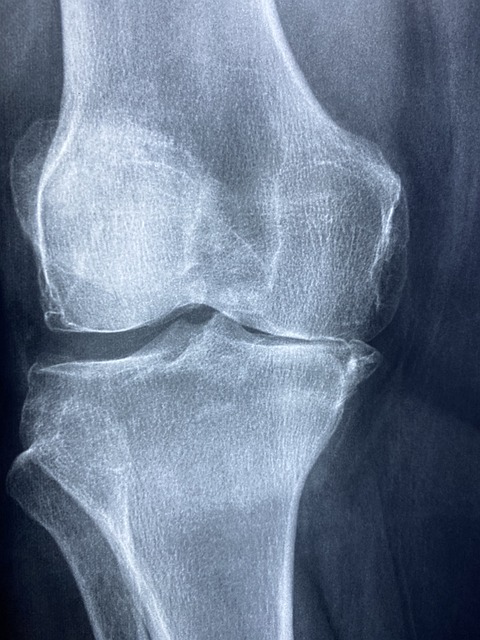

류마티스 관절염은 자가면역 질환으로 면역체계가 정상 조직을 공격해 발생하는 만성 염증성 질환입니다. 주로 관절의 통증과 붓기를 일으키며, 조기에 발견하고 치료하는 것이 중요합니다. 류마티스 관절염 초기증상, 치료법, 자연 치유 가능 여부, 그리고 추천 운동까지 자세히 알아보겠습니다.

류마티스 관절염의 초기 증상

류마티스 관절염의 초기 증상은 일반적인 관절 통증과 비슷해 많은 사람들이 쉽게 지나칠 수 있습니다.

하지만 증상이 나타난다면 류마티스 관절염을 의심해보고 진료를 받는 것이 좋습니다.